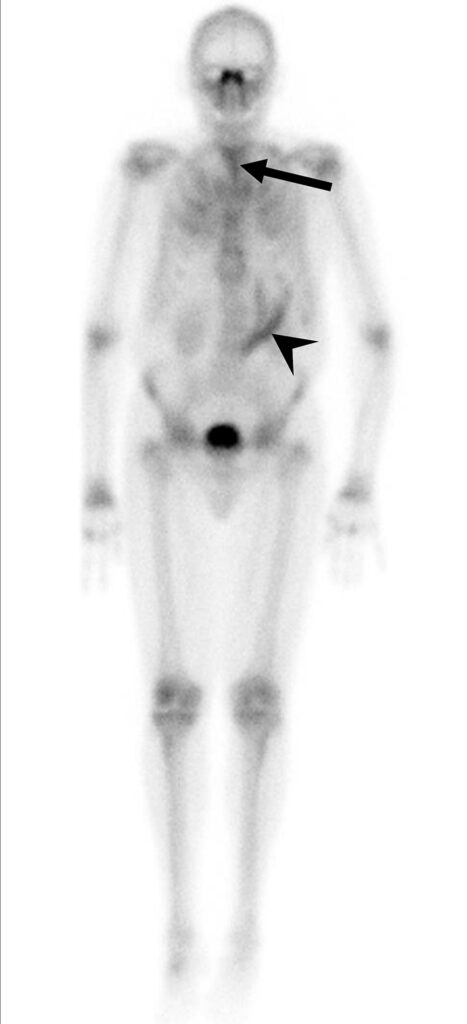

Uomo di 72 anni con artrite reumatoide sieropositiva (in terapia biologica) e dolore cervicale. Un iniziale reperto RM aveva posto il sospetto di un’infezione a livello dell’articolazione atlanto-assiale. Il paziente è stato sottoposto a scintigrafia ossea trifasica con 99mTc-MDP.

L’immagine whole-body di blood-pool (a) ha mostrato un aumentato accumulo del tracciante in entrambe le articolazioni delle spalle, nell’articolazione sternoclaveare destra, in entrambi i polsi, nel ginocchio destro e nelle piccole articolazioni di mani e piedi. L’immagine whole-body tardiva (b) ha evidenziato un’aumentata concentrazione del tracciante nelle medesime regioni che mostravano un aumentato accumulo ematico. La SPECT-TC della regione testa-collo ha mostrato un’aumentata captazione del tracciante lungo le faccette di sinistra tra le vertebre C1 e C2 (c) e nell’articolazione sternoclaveare destra (d), quadri interamente riconducibili ad artrite reumatoide attiva.